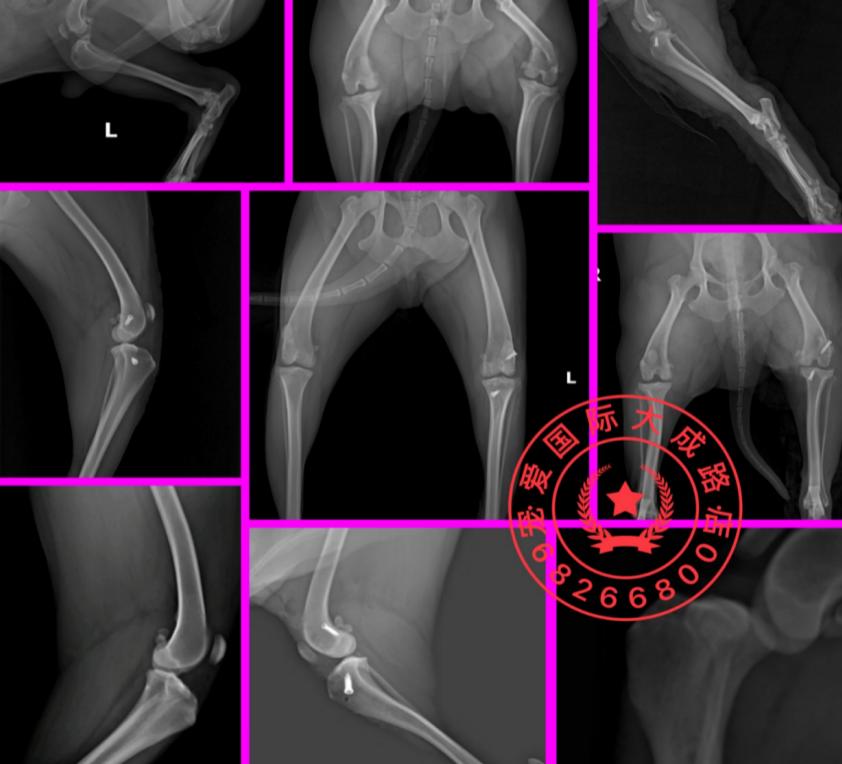

DR检查

右后肢股骨滑车脊的关节周围有新骨生成。

髋关节腹背位↑

左、右后肢侧位 片 关节腔内软组织不透明度增加,膑下脂肪垫向前位移;

左后肢前后位↑

左后肢内外位↑

正位片可见关节内侧软组织不透明度增加;胫骨粗隆前移。

右后肢前后位↑

右后肢内外位↑